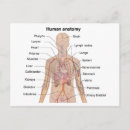

Human Yta Anatomy Relation till organ Poster

Pris258,00 kr

Human Yta Anatomy Relation till organ Poster

Pris258,00 kr

Anatomi i mänskliga organ vykort

Pris23,00 kr

Anatomi i mänskliga organ poster

Pris229,00 kr

Anatomi i mänskliga organ canvastryck

Pris1 425,00 kr

Anatomi i mänskliga organ hälsningskort

Försäljningspris 49,00 kr. Ursprungligt pris 54,00 kr.